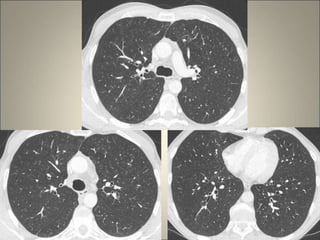

Œdème interstitiel et alvéolaire sur BPCO

2006 8/2015 01/2016

03/2016

Œdème interstitiel etalvéolaire sur BPCO 2006 8/2015 01/2016